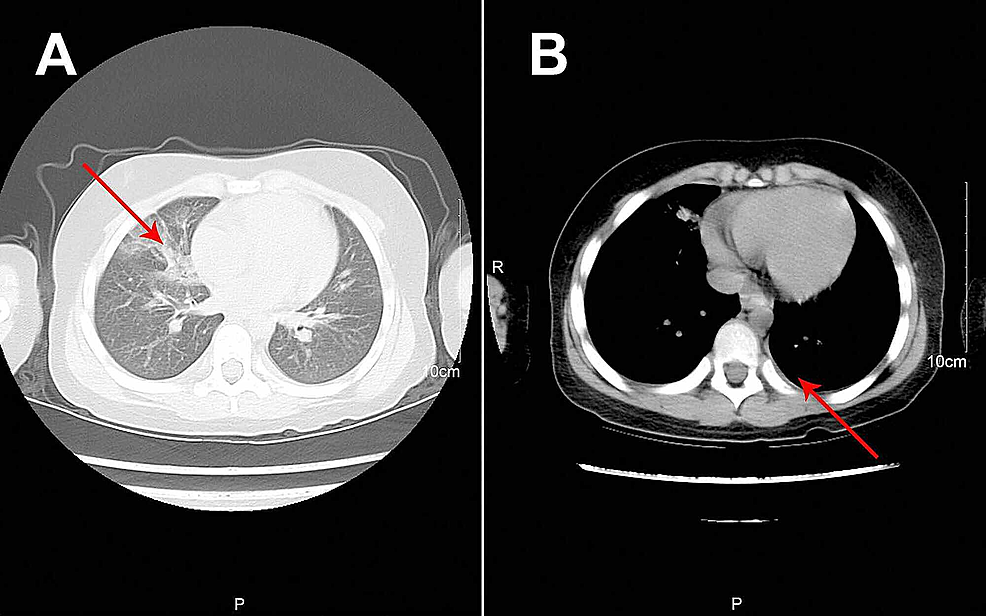

Treatment regimens were adjusted based on the etiological results. Imipenem-cilastatin sodium and vancomycin were discontinued; further, the patient was administered with piperacillin (50 mg/kg, bid), and added Oseltamivir for anti-influenza A virus. Azithromycin (10 mg/kg, qd), intravenous methylprednisolone (1 mg/kg, q12h), nebulized dexamethasone (5 mg, q6h), nebulized bronchodilators, intensive chest physiotherapy, and intravenous mucosolvan were continued. However, there was still no improvement. Considering the histopathology showed the casts predominantly comprised of mucin, and the mucolytic agent mucosolvan, as well as bronchodilators, were not effective, we used a mucolytic agent-α-chymotrypsin, which has been reported to liquefy the mucus. α-chymotrypsin (2000 IU, 5 mL saline) was intratracheally instilled twice a day via the endotracheal tube, supplemented by frequent intratracheal suction and chest physiotherapy. Consequently, abundant purulent secretions and casts were discharged (Figure 2B); further, the oxygen saturation increased to 93% and there were enhanced breath sounds in both lungs. The patient was successfully extubated with gradual improvement in his condition. Subsequently, the patient received oral azithromycin (10 mg/kg, three times per week) and nebulized budesonide (1 mg added in 2 mL saline, twice daily). Chest CT reexamination showed the full expansion of the left lung with pleural effusion on the left thorax and bilateral pneumonia (Figure 3A). Additionally, fiberoptic bronchoscopy revealed endobronchial intima infection without casts (Figure 4). After six days, he was discharged with a little cough and no neurological sequelae; continued on oral azithromycin and nebulized budesonide treatment for two weeks. The timeline of this case was shown in Figure 5. During the next four follow-up visits, the patient was asymptomatic and without recurrent casts. Further, his chest CT scan showed increased lung markings (Figure 3B).